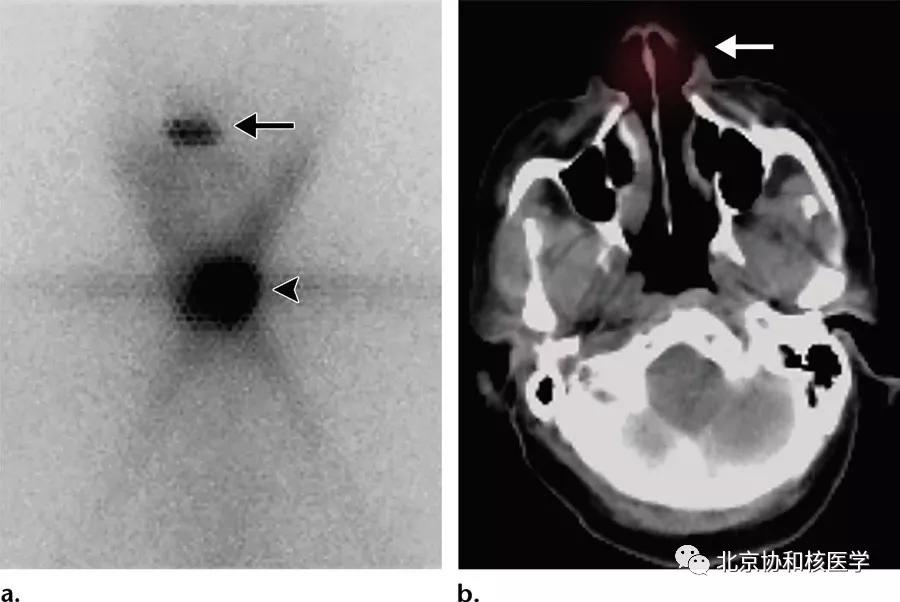

脑膜瘤所致碘摄取:

鼻骨骨样骨瘤所致碘摄取,腹部另可见由于巨大肾囊肿所致碘异常摄取: